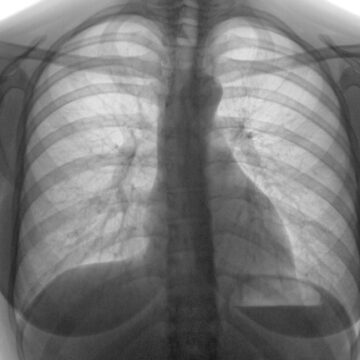

La Organización Mundial de la Salud (OMS) ha elaborado un manual operativo sobre latuberculosis (TB) a fin de proporcionar asesoramiento práctico que complemente a la actualizacióndel 2022 de las más recientes Directrices unificadas de la OMS sobre la tuberculosis (denominadasen adelante las “directrices unificadas de la OMS”). En el presente documento se ofrece informaciónsobre la...

Tag: tuberculosis